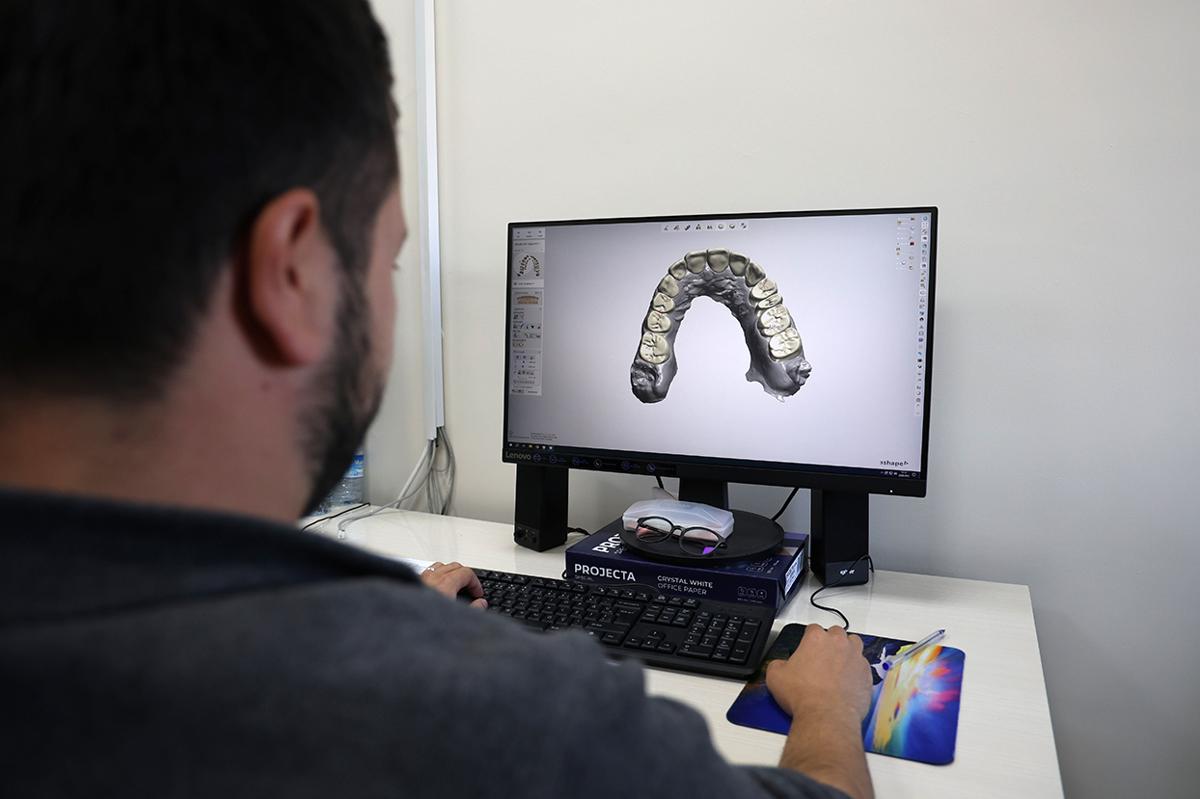

SON TEKNOLOJİ CİHAZLAR İLE KISA SÜREDE YAPILIYOR

Zirkonyum kaplama kararı alınan hastaların çene ve diş yapısı kamera yardımı ile taranıyor. Dijital ortama aktarılan görsellere kişiye özel tasarım yapılıyor. Tasarım aşaması tamamlanan görseller, zirkonyum bloklara işleniyor. Bloktan çıkarılan kaplamalar, özel fırınlarda dayanıklılık kazanıyor. Makyaj aşaması tamamlanan zirkonyum kaplamalar, kullanıma hazır hale getiriliyor. Söz konusu kaplamalar, emekli vatandaşlara 95 TL, çalışanlara ise 188 TL maliyet oluşturuyor.

Zirkonyum kaplamalara ilişkin bilgiler veren Sivas Ağız ve Diş Sağlığı Hastanesi Başhekimi Diş Hekimi Fuat Şen, "Zirkonyum porselenin daha estetik ve daha sağlam bir şekilde dijital ortamda elde edilmesi, daha öncelerde hizmet ihalesiyle aldığımız zirkonyum dişleri artık hastane bünyesinde kendimiz oluşturuyoruz." dedi.

Başhekim Şen, "Modern laboratuvarlarda dijital sistemler kullanarak hazırlanan zirkonyum restorasyonlar doğal dış görünümüne en yakın sonuçları sunarken uzun ömürlü bir kullanım sağlar. Hastanemizde bu imkân bakanlık onayı ile ilk defa Sivas Ağız ve Diş Sağlığı Hastanesi olarak gerçekleştirildi ve hayal diye nitelendirilen laboratuvar, tüm Türkiye tarafından da takip edilen bir merkez haline gelmiştir." sözleriyle açıklamasını sürdürdü.

Bilgisayar destekli zirkonyum diş kaplaması tasarımı. (Ali Aydın, Rahmi Meyveci / İHA)

Başhekim Şen, "Ağız içerisinden dijital ortamlarda ölçülerimizi alıp bilgisayarlara aktarma yapıyoruz. Daha sonra tasarlanan zirkonyum bloklarımızı kazıyıcı sistemle oluşturuyoruz. Oluşan protezleri fırınlarda pişirerek son halini alıyoruz. Renklendirme işlemleri sonrasında 48 saat içerisinde hastamıza teslim ediyoruz. Daha sağlıklı, doğal ve estetik dişler için zirkonyum diş teknolojisini artık kolay ulaşılabilir hale getirmiş olduk. Yurtdışından gelen vatandaşlara da bu hizmeti sunmuş oluyoruz. Tüm vatandaşlara hayırlı uğurlu olsun" şeklinde konuştu.